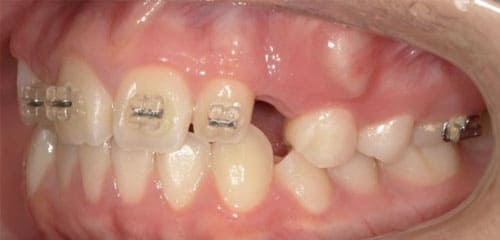

● 歯根が折れ保存不可の歯を抜歯して、そのスペースに八重歯を並べた症例

藤沢デンタルオフィスの虫歯や破折で抜歯後の部分矯正